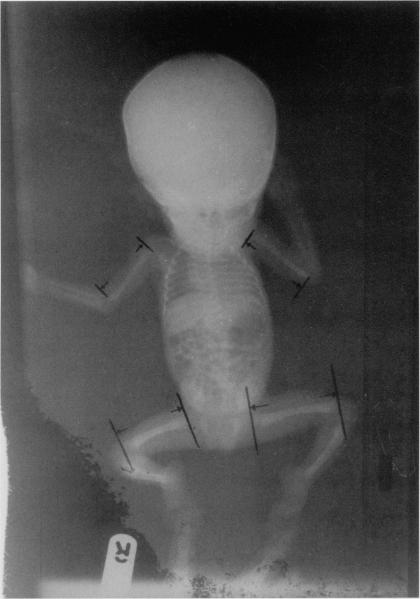

Russell-Silver Syndrome (RSS) is a rare cause of pre-natal dwarfism, associated with recognizable dysmorphic features and limb asymmetry. The propositus was a term infant of unrelated Nigerian parents, whose 35-year-old mother had peri-conceptual haloperidol for schizophrenia. Anthropometric values suggested severe prenatal stunting in a term infant with asymmetric "head sparing" intrauterine growth retardation (IUGR). A syndromic consideration of Russell-Silver dwarfism was subsequently predicated on the distinctive dysmorphic craniofacial features of a triangular facial profile with a broad forehead and hypoplastic mandible, right upper and lower limb rhizomelia, clinodactyly of the little fingers, micro-penis, and (unilateral) cryptochidism. Routine care of a small-for-gestational-age infant was pursued, but postnatal growth remained slow (despite adequate caloric provision) until a parent-pressured discharge at 4 weeks. His subsequent demise was said to have occurred "suddenly" 2 weeks post-discharge. Despite the limitations posed by the local paucity of modern investigative tools for genetic disorders, the current case report underscores the diagnostic reality of RSS in a non-white African population. While emphasizing the need for a high index of diagnostic suspicion for congenital malformations and syndromic causes of IUGR in the African sub-region, we suspect a possible etiologic association of haloperidol embryopathy with RSS in the current case. The characteristic features, differential diagnoses, etiologic postulates/current cytogenetic and molecular genetic findings of RSS are fully reviewed in the discussion.